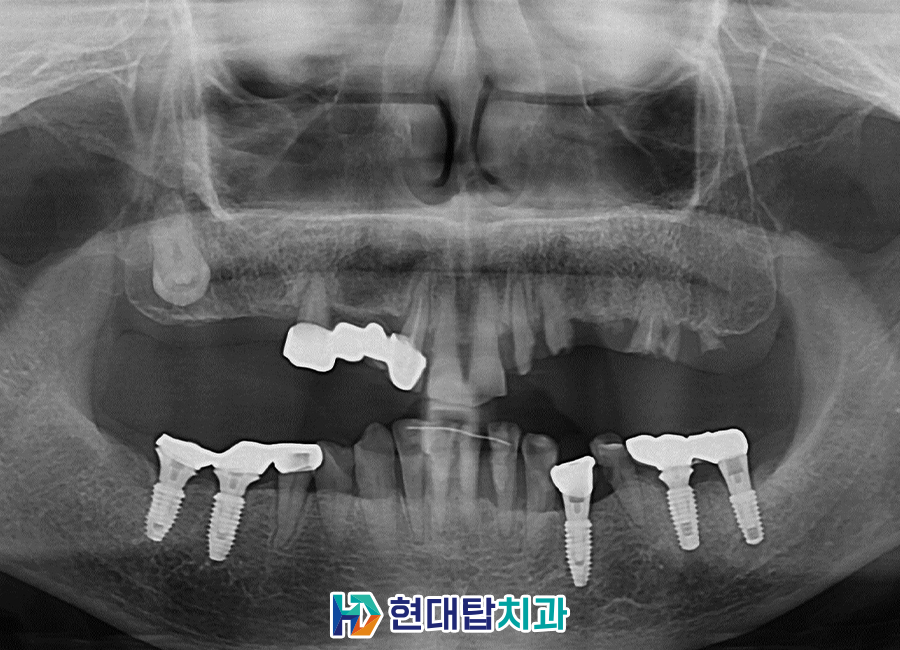

위 환자분은 52년생의 여성분으로

타원에서 진행하신 임플란트와 틀니를

사용 중이셨는데 틀니를 지지해 주던

치아가 파절되어 내원해 주셨습니다.

기존의 틀니를 사용하실 때부터

불편함이 많이 있으셨다고 하셔서

양쪽 위 8개의 임플란트를 식립하여

11개의 치아를 연결하는 브릿지의 형식으로

진행하기로 하셨고, 상태가 좋지 않던 오른쪽 아래

작은 어금니들은 신경치료 후 보철을 진행하였습니다.

또한 기존의 타원 임플란트 들의 보철물을

식립 예정인 임플란트와 교합이 잘 맞을 수 있도록

교체하도록 설명드렸고 치료 계획 수립하였습니다.

술후 파노라마입니다.

치아의 갯수가 많이 없다 보니

전체적으로 치아의 씹는 균형이 많이 무너진 상태여서

차근차근 맞춰가며 최종 보철까지 문제없이 합착하였습니다.

또한 예후가 불량했던 오른쪽 아래

작은 어금니들도 신경관 내부를 단단한 재료로

메워 신경치료를 진행한 후 보철까지 완료하었습니다.